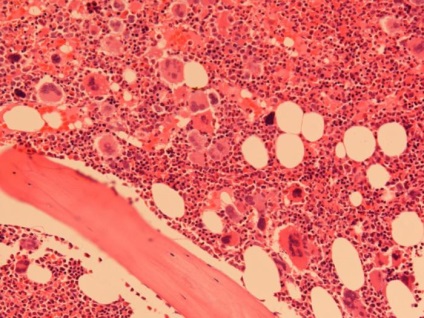

Myeloma (mielomatoz, plazmacitóma, retikuloplazmotsitoz) - egy rosszindulatú daganat, amely egy csoporthoz tartozik a hematológiai rosszindulatú betegségek. Ebben a betegségben, a kórosan proliferáló sejtek plazma sejtek - a reakció végtermékei a B-limfociták, amelyek normálisan antitesteket termelnek, amelyek kulcsszerepet játszanak az immunválaszban.

Myeloma alakul mutációja miatt érett plazmasejtek hatása alatt tényező a tumornövekedés (interleukin-6). Proplazmatsita patológiai változás hatására a tumor alkotnak egy klón, amely nem érzékeny a apoptózis és szaporodnak kontrollálatlan. Mivel egyre több rosszindulatú sejtek növekvő koncentráció és patológiás immunglobulin általuk előállított (paraproteinnel).

A kóros sejtek szaporodásának neoplasia fokozatosan felváltja a funkcionalitás. Ugyanakkor gátolja a termelés minden típusú vérsejt, amely anémiához, csökkent véralvadás és immunitás rendellenességek.

A jellemző áramlási mielomatoza feloldja a csont szakaszok helyén a patológiás sejt lokalizáció. A folyamat az élet megváltozott plazmasejtek citokineket, amelyek aktiválják az osteoclastok - különleges sejtek, amelyek részt vesznek a folyamatban csontforgalom. Amikor az egyensúly az osteoblast és osteoclast aktivitást mellett az első oldódási sebessége az ásványi komponens a csont-kollagén és megsemmisítése sokszor a képződési sebességét új szövet. Ezáltal zsebek felszívódást (megszüntetés), az érintett csontok törékennyé válnak és törékeny.